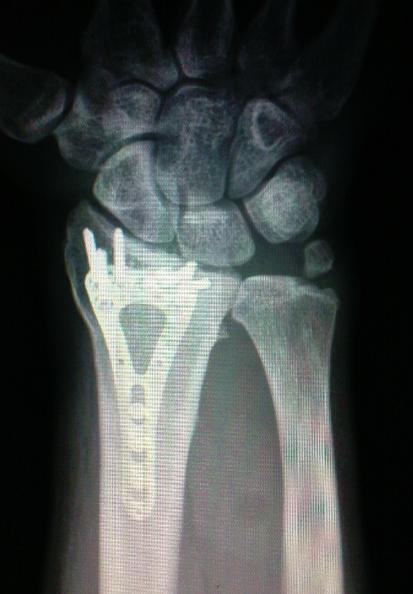

Hele pankáči,dneska jsem byl na tom pražským lontu v ÚVN na kontrole a čumte,co mám v ruce:

Mr GS přiložený následující obrázek:

Tak to bud rád že nemáš rentgen hlavy!!hilarious

Ty vole to vypadá jak votvírák na lahváče.Grin